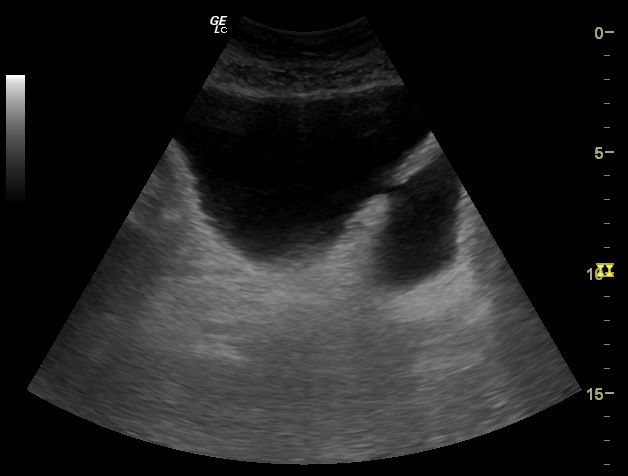

Glándula prostática de 4,28 x 5,81 x 4,57 cm (Figura 1). Volumen prostático: 59,45 ml. Pared de vejiga no engrosada. Se objetiva divertículo vesical (Figura 2) único localizado en pared postero lateral. No se observan lesiones intravesicales ni tampoco en la luz del divertículo (Figura 3). Volumen posmiccional 240 cc.